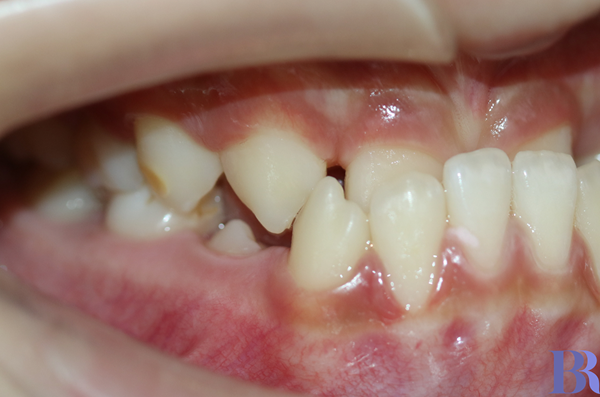

교정 전 오른쪽 모습

반대교합 양상이 심한 것을

알 수 있습니다.

과연 교정으로만 해결할 수

있을까 싶을 정도입니다.